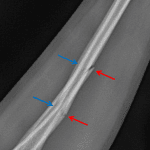

- Acute greenstick fractures of the mid radial and ulnar diaphyses with apex volar angulation

- Greenstick fractures

Acute greenstick fractures of the mid radial and ulnar diaphyses with apex volar angulation.

Alignment appears maintained at the elbow and wrist, though dedicated elbow and wrist views could further assess.

- Greenstick fractures occur in young children and are often diaphyseal

- The fracture occurs along the tensile side but does not extend to the compressive side of the bone

- While these are often managed conservatively, fractures with too much angulation (e.g. > 20 degrees) may require surgical management